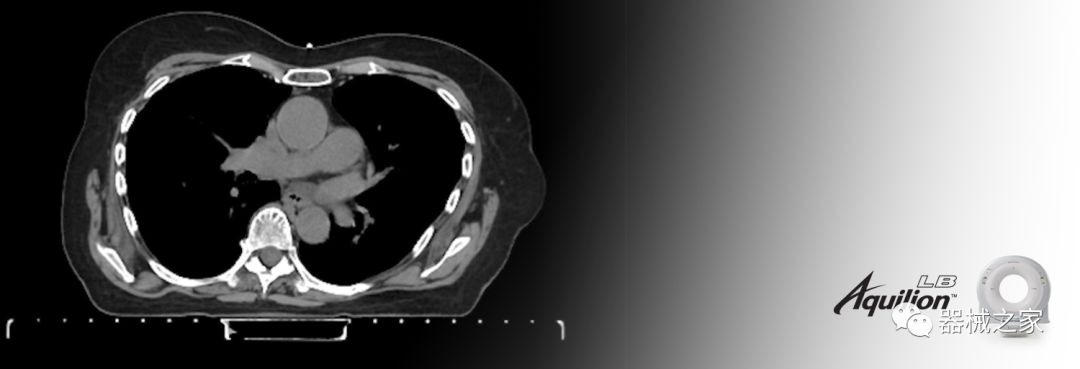

佳能醫(yī)療的Aquilion Lightning 80掃描儀還以緊湊,經(jīng)濟的包裝提供高質(zhì)量的成像。Aquilion Lightning 80旨在可靠,高效地運行,在繁忙的環(huán)境中生成高質(zhì)量的圖像。

Aquilion LB專為滿足腫瘤學挑戰(zhàn)而設(shè)計,同時優(yōu)先考慮患者護理。Aquilion LB的內(nèi)徑為90 cm,能夠幫助復(fù)雜的患者設(shè)置并提高患者的舒適度。CT模擬定位可以輕松鏡像放射治療定位,更加自信。該系統(tǒng)采用0.5 mm x 16排(32層)PUREViSION探測器技術(shù),70 cm視野,AIDR 3D和SEMAR技術(shù)。